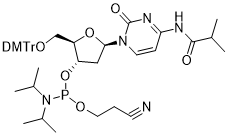

馬鞍山致研生物醫(yī)藥科技有限公司成立于馬鞍山市鄭浦港新區(qū)現(xiàn)代產(chǎn)業(yè)園。公司專(zhuān)注于生物小分子、醫(yī)藥中間體相關(guān)產(chǎn)品的研發(fā)和生產(chǎn),產(chǎn)品主要包括DNA亞磷酰胺單體、RNA亞磷酰胺單體、特殊單體以及按照客戶(hù)要求定制的RNA和DNA,并且公司提供定制合成等方面的研究服...

馬鞍山致研生物醫(yī)藥科技有限公司成立于馬鞍山市鄭浦港新區(qū)現(xiàn)代產(chǎn)業(yè)園。公司專(zhuān)注于生物小分子、醫(yī)藥中間體相關(guān)產(chǎn)品的研發(fā)和生產(chǎn),產(chǎn)品主要包括DNA亞磷酰胺單體、RNA亞磷酰胺單體、特殊單體以及按照客戶(hù)要求定制的RNA和DNA,并且公司提供定制合成等方面的研究服...